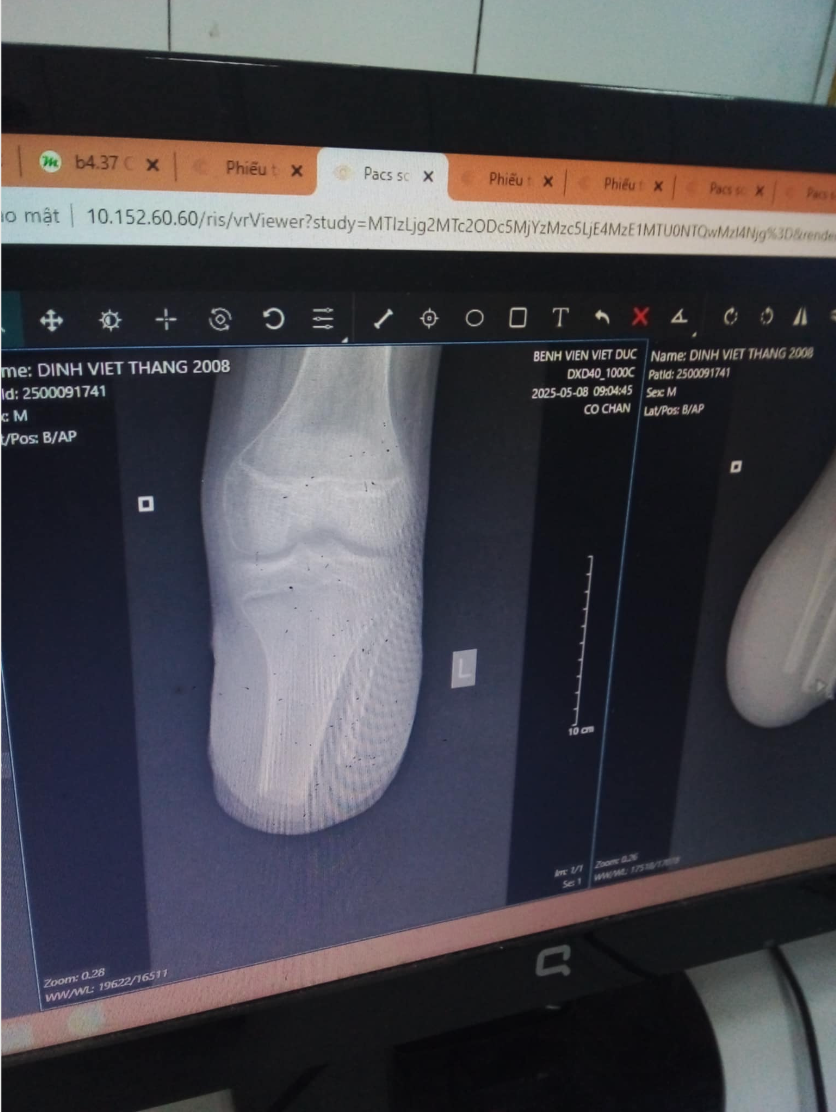

Nga´s Sohn Thang, der jetzt in der 11. Klasse ist, ist vor einem reichlichen Monat so schwer mit dem Motorbike verunglückt, dass ihm in einer Klinik in Hanoi ein Teil seines Beines amputiert werden musste. Er hat bereits etliche Operationen hinter sich. Dass die medizinische Versorgung und finanzielle Absicherung in Vietnam keinesfalls vergleichbar ist mit Deutschland, kann sich jeder vorstellen.

Um wieder „auf die Beine zu kommen“, benötigt er eine Prothese. Das ist für die Familie eine Kostenintensive und fordernde Angelegenheit. Schon jetzt übersteigen die Kosten für die OPs das Budget der Familie. Thangs Eltern übernachten zur Zeit auf Bambusmatten im Krankenzimmer ihres Sohnes, im Krankenhaus von Hanoi. Die Arbeitsausfälle der Eltern schlagen da nochmal zusätzlich auf den Geldbeutel der Familie.